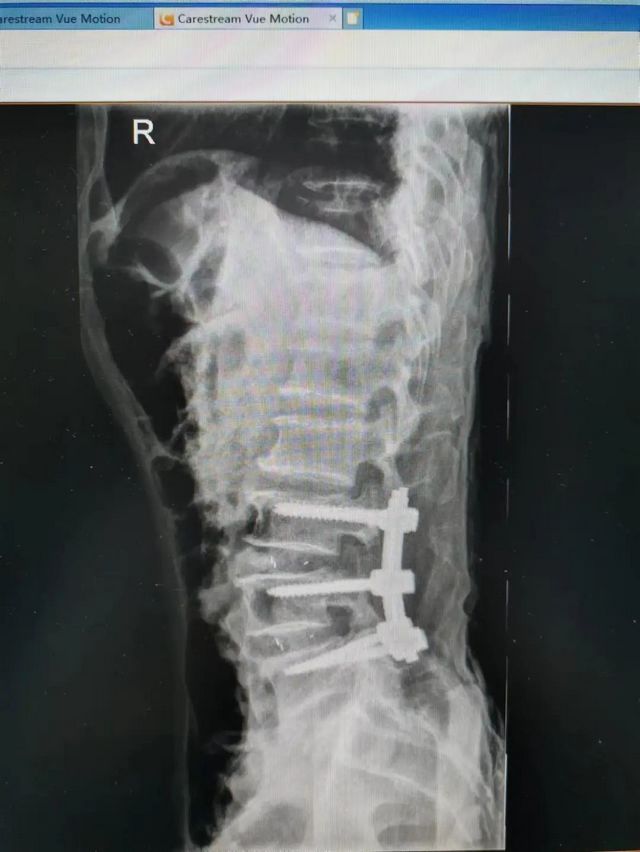

杨先生术后拍片

由于杨先生的病情严重,需住院治疗。杨先生入院后,泸州市中医医院骨伤二科科主任杨陈一制定了手术计划,决定脊髓型颈椎病的手术从前路切开减压,颈3/4 、颈4/5、 颈5/6、 颈6/7椎间盘切除,椎间融合,钢板内固定术手术,而腰椎管狭窄症经后路切开减压,腰3/4、腰4/5椎同盘动除,椎间融合、钉棒系统内固定术。